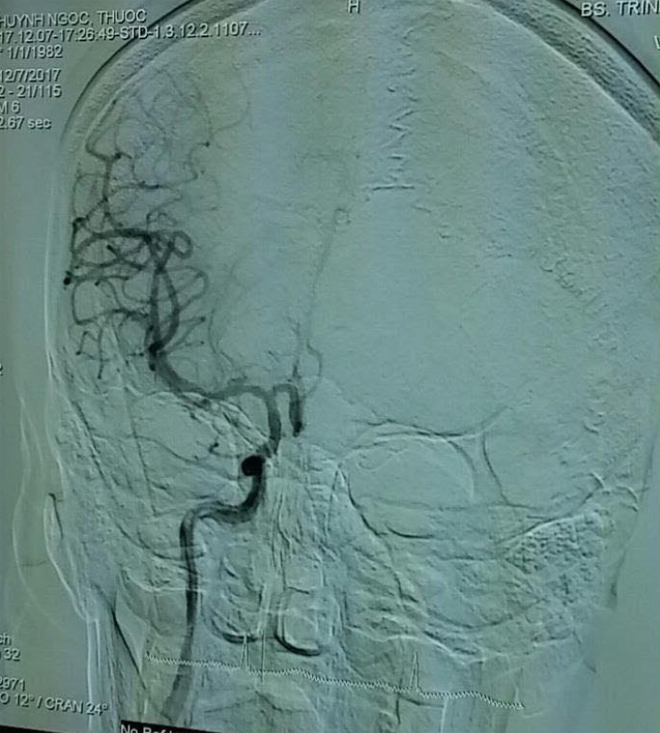

![]() |

| Hình ảnh sau can thiệp lấy huyết khối mạch máu não cho bệnh nhân T.. |